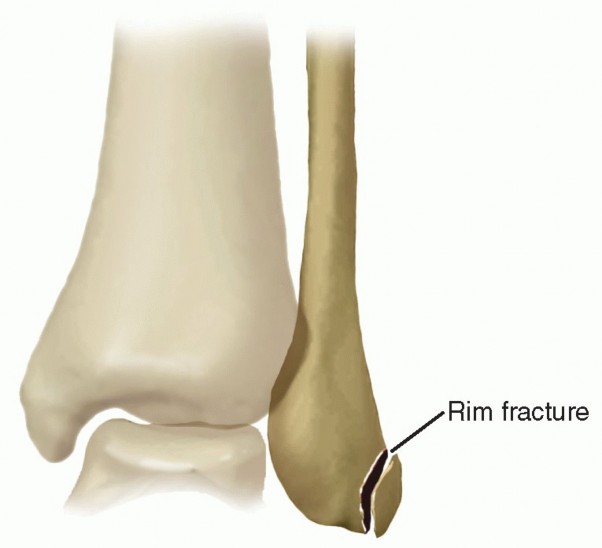

| Routine ankle radiographs are essential to identify or rule out a rim fracture of the distal fibula, which occurs in 15% to 50% of all cases of peroneal subluxation.1 | |||

| Standard weight-bearing ankle radiographs (anteroposterior [AP], lateral, and mortise) define the bony ankle anatomy alignment. In cases of peroneal tendon subluxation, radiographs are usually negative. In a grade 3 injury, a “fleck” of bone can be seen off the posterior distal fibula and is considered pathognomonic of an SPR injury (FIG 3). | |||

Grade 3 injury: avulsion of a thin fragment of bone along with the collagenous lip attached to the deep surface of the SPR and deep fascia (Radiographically, this may be represented by a “fleck sign.”)